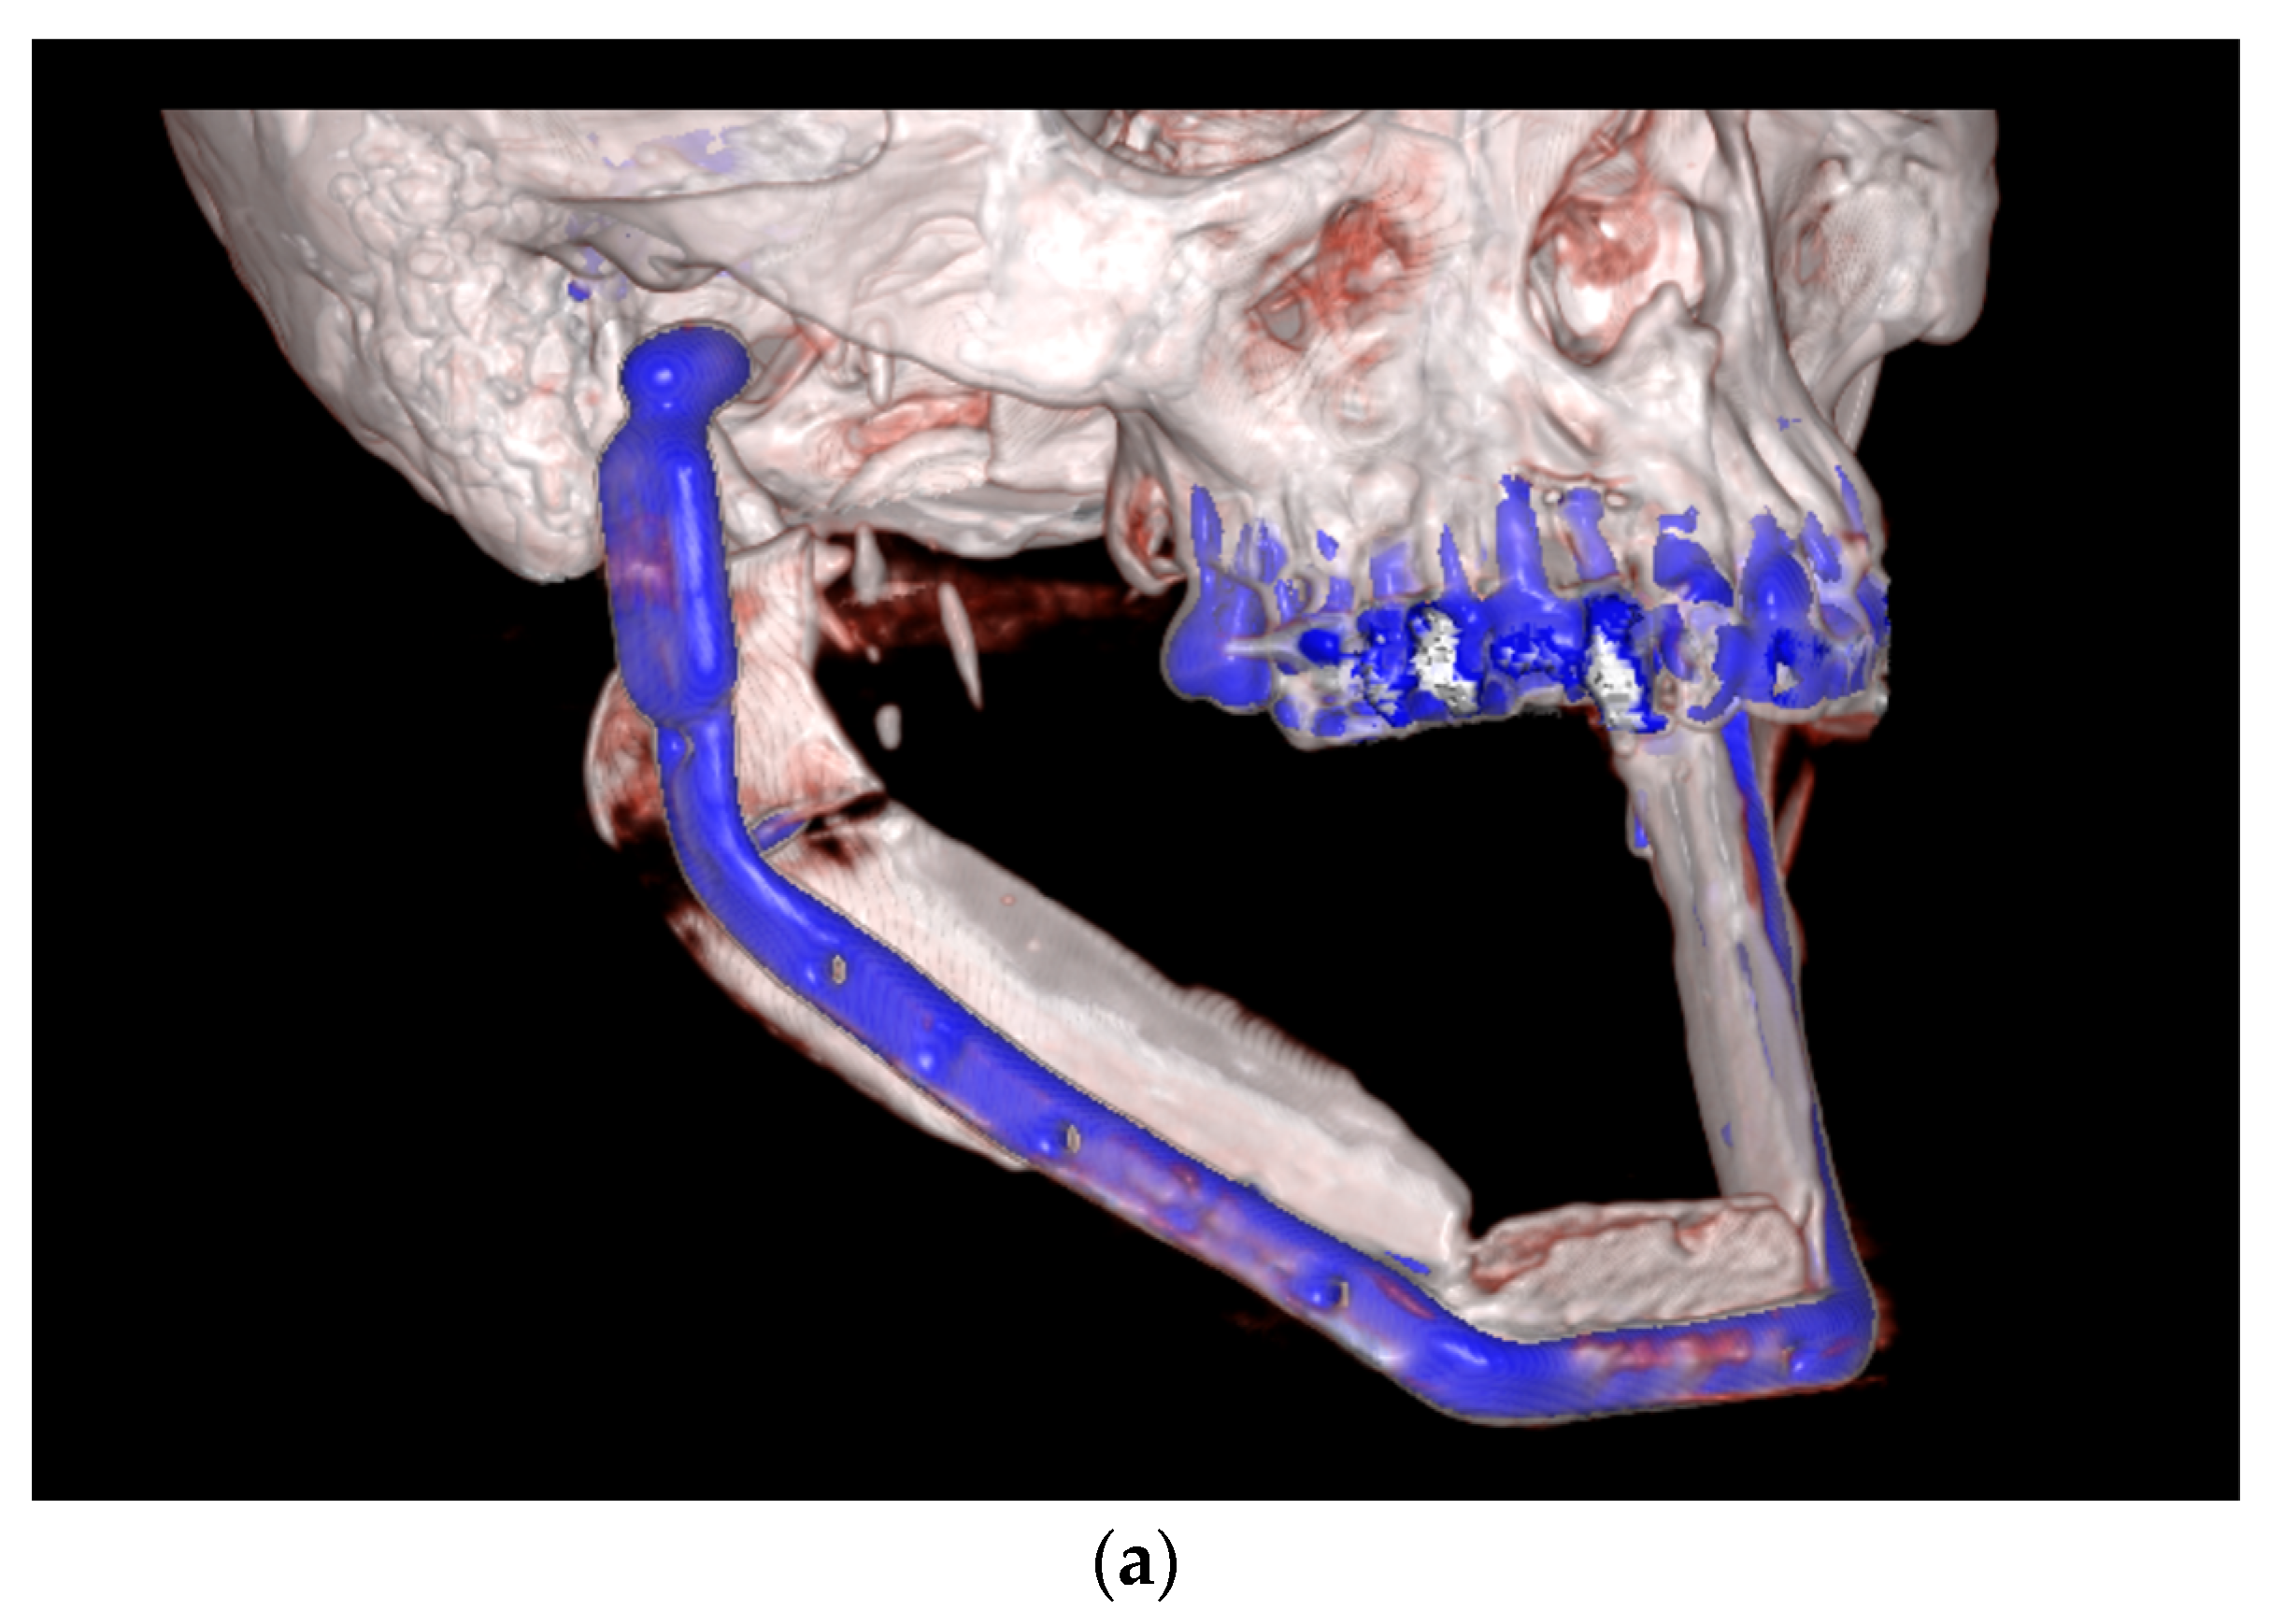

| September 2022: | Partial mandibular resection from the left mandibular angle to the right mandible, including the right temporomandibular joint, CAD/CAM-guided reconstruction with a bilateral free scapula flap with skin island, and patient-specific plate. In the course: